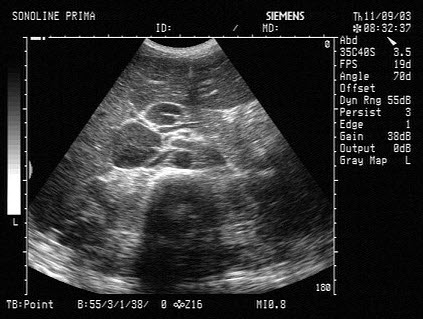

9、单项选择题

男,有胃癌手术史。根据超声声像图诊断为()

A.脾梗死

B.脾淋巴肉瘤

C.脾错构瘤

D.脾转移性癌

E.脾血管瘤